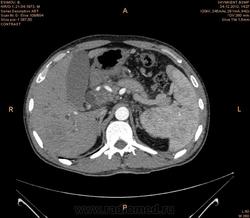

Предварительно образование головки ПЖ, и в печени. Что с ферментами?

на операций рак головки подж.железы с метастазир. печень.

инфильтрация тут нисходящей 12 перст кишки , расширенного холедох,расширенный вирсунгов проток ,нижная граница очень близко прилежит к нижней полой вене с правой почечной веной ,но четко визуализирутся передний листок фасции Героты(нельзя исключить ее инфильтрацию), инфильтрация конгломератом увеличенных лимфатических узлов ворот печени портальной вены с варикозным расширением вен, на вышележащий срезах четко определяются верхняя брыжеечная вена и артерия ,не хватает срезов для полной визуализации(помогли бы мпр),инфильтрирована восходящая ободочная кишка,конгломерат лимфат узлов за головкой поджелудочной железы в виде гиподенсивного участка вытянутой формы , ,мтс в печень,парааортальные